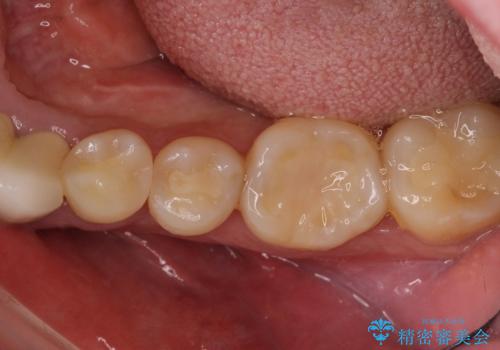

奥歯で噛みたい インプラントによる欠損補綴治療

- 抜歯をしたものの、インプラントにするか入れ歯にするか悩んでいるうちに2年以上経過してしまったとのことで来院された患者様です。

自分の歯のように噛めるようにしたいとのことで、インプラントによる欠損補綴治療を行うこととしました。

インプラントにはストローマン社のSLActiveを使用し、埋入から補綴までおよそ3か月と、短期間で治療を進めることができました。